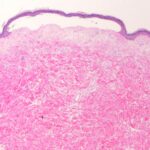

In epidermal EB, which includes EB simplex, EB offeet and hands of Weber and Cockayne , and EB herpetiform is (Dowling-Meara) , the primary separation in experimentally induced blisters always occurs within the basal cell layer. Spontaneously arising blisters may be found subepidermally as the result of complete disintegration of the basal cell layer; in bullae of more than 1 day’s duration, the cleavage may be found intraepidermally or subcorneally as a result of epidermal regeneration . In sections stained with the PAS technique, the PAS-positive basement membrane zone is located on the dermal side of the blister . |

In junctional EB, the trauma of having a specimen taken for biopsy generally is sufficient to induce separation. This separation is located between the epidermis and the dermis, with |

the PAS-positive basement membrane zone usually remaining with the dermis . In some cases of EB letalis, autopsy has revealed extensive subepithelial separation also in the gastrointestinal, respiratory, and urinary tracts . There are no morphologic or enzymatic abnormalities to distinguish the atrophic benign form of junctional EB from EB letalis . |

In EB dystrophica-dominant and EB dystrophica-recessive, light microscopy shows dermal-epidermal separation. A PAS stain is of little help in ascertaining the exact level of cleavage because the PAS-positive basement membrane zone often appears hazy . If recognizable, it is seen in contact with the detached epidermis or appears split. In EB dystrophica-dominant, scarring is mild. However, in generalized EB dystrophica-recessive, extensive erosions may occur, resulting in ulcerations and severe scarring. Severe oral involvement can lead to esophageal stenoses (181). In especially severe cases, death may occur. The ulcers and scars of the skin, mouth, and esophagus may give rise to squamous cell carcinomas, which tend to metastasize . |